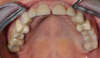

Restauration complète maxillaire et mandibulaire

Eclaircissement et couronnes céramo-céramiques